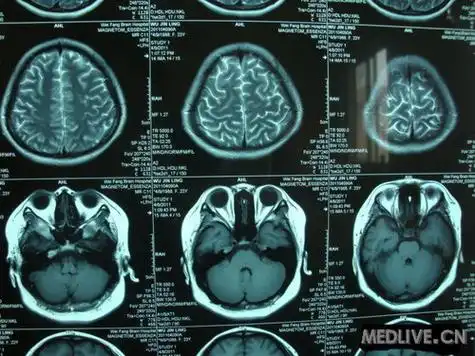

苯巴比妥在防治新生儿窒息后脑损伤中的作用研究